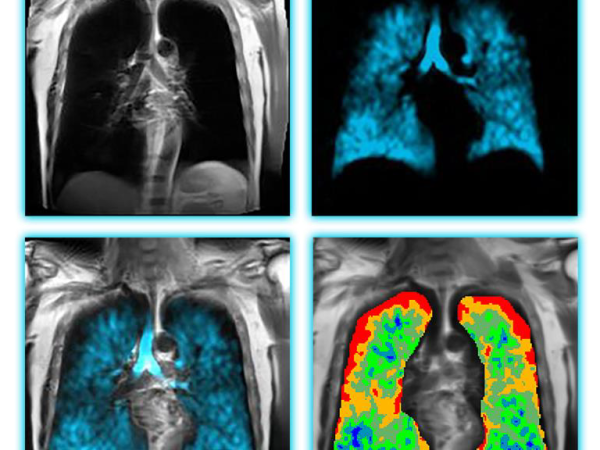

上鉅實業引進革命性Xenon MRI氙氣磁振造影肺部功能成像平台,推動台灣呼吸醫學新紀元

Polarean Imaging 公司與上鉅實業股份有限公司2025/3/2正式簽署代理協議,將Polarean創新性的氙氣Xenon MRI平台引進台灣。